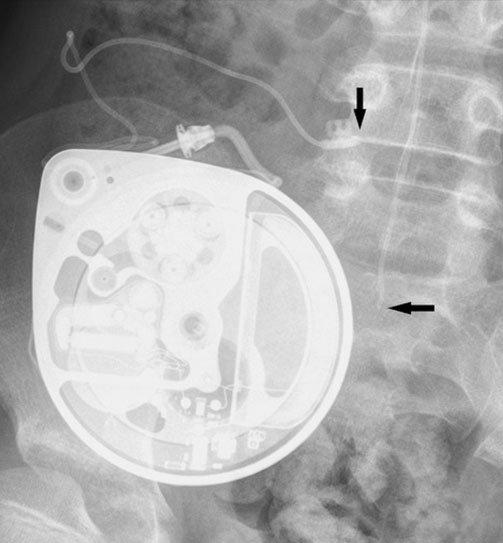

Intrathecal Pump Placement

Intrathecal pumps deliver medication directly into the cerebrospinal fluid (CSF) surrounding the spinal cord. These devices are connected to fine tubes placed into the CSF. This form of neuromodulation allows for delivery of opioids in chronic pain conditions including cancer pain.

This form of therapy requires a test phase to check drug efficacy before an implantation phase is undertaken. These procedures are always in-hospital procedures and are performed in an operating room environment under general anaesthesia. During such a procedure the catheter tube and pump device are implanted into the body. This form of therapy is only applicable for long-term symptom management.